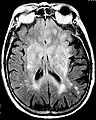

Fluid-attenuated inversion recovery (FLAIR) is an MRI sequence with an inversion recovery set to null fluids. For example, it can be used in brain imaging to suppress cerebrospinal fluid (CSF) effects on the image, so as to bring out the periventricular hyperintense lesions, such as multiple sclerosis (MS) plaques.[1] It was invented by Graeme Bydder. FLAIR can be used with both three-dimensional imaging (3D FLAIR) or two dimensional imaging (2D FLAIR).